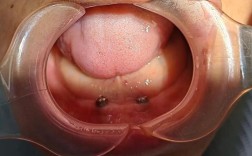

种植牙的结构分解

| 组件 | 典型材料 | 是否含金属 | 对CT的影响程度 |

|---|---|---|---|

| 种植体 | 医用纯钛 / Ti-6Al-4V合金 | ||

| 基台 | 钛合金 | ||

| 牙冠 | 全瓷(氧化锆)、树脂 | 视材料而定 | |

| 注:部分临时冠可能含金属内核 |

👉 关键点:只有直接暴露于X射线路径上的金属部件才会产生明显伪影,深埋于牙槽骨内的种植体由于周围骨组织的包裹,其产生的伪影强度远低于口腔内可见的金属冠桥。